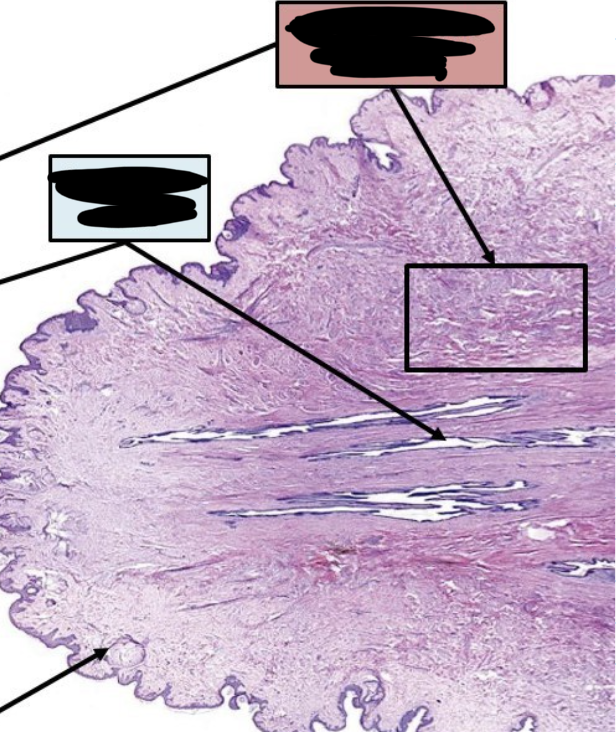

label this slide

transformation zone (to stratified squamous non keratinized epithelium)